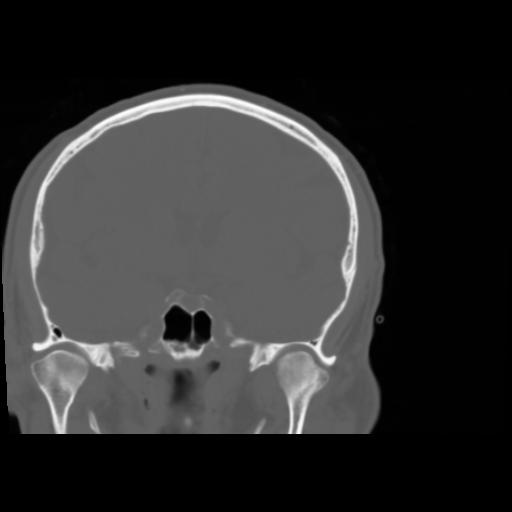

5 CEREBRO,,Coronal,3.000,CEREBRO,Coronal,